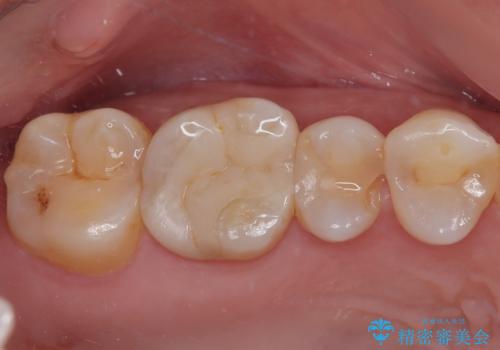

- セラミックインレー

- 2009~2025年6月

- 000本

最新の症例

Latest cases